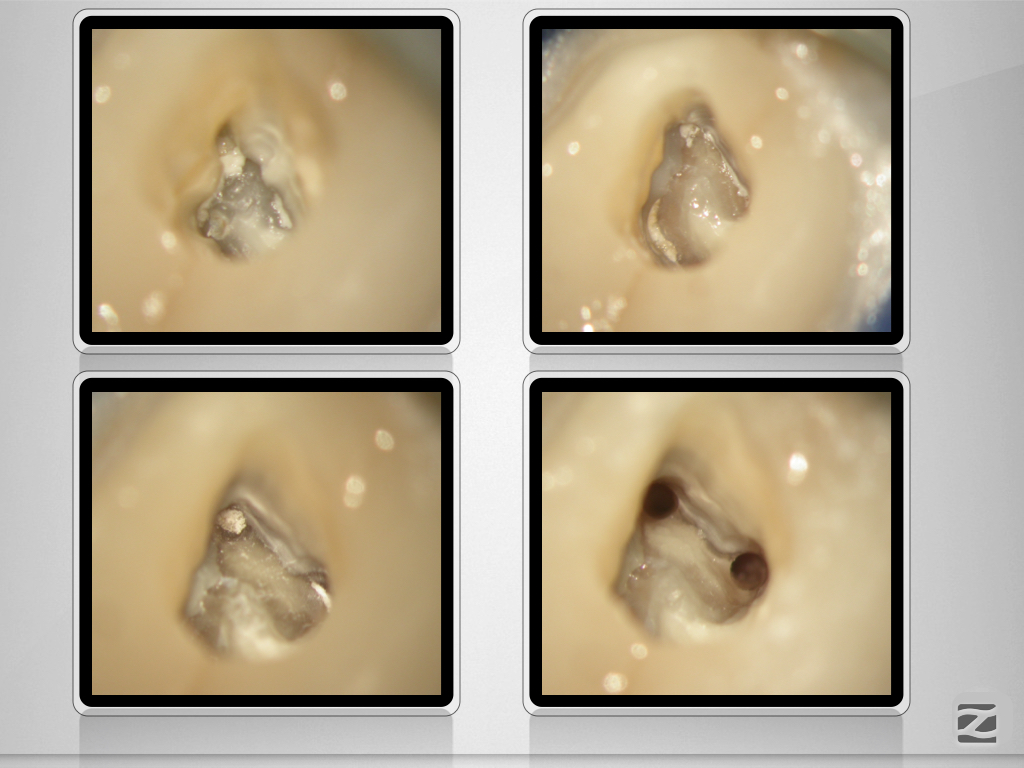

26D.008 Veröffentlicht 12. Februar 2021 am 1024 × 768 in Tiefe Aufgabelung, zwei Fisteln und ein Recall